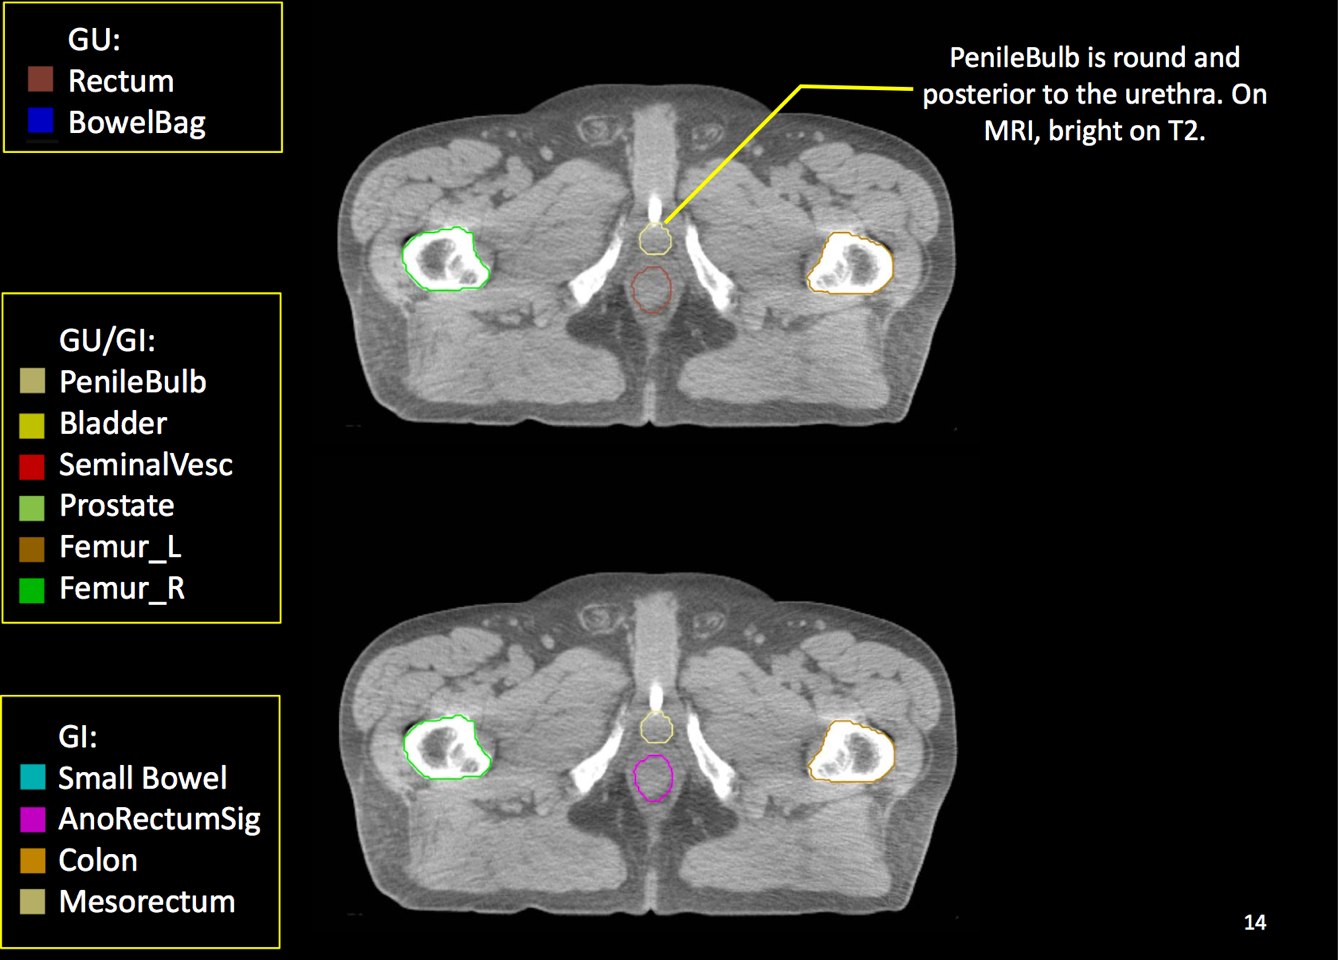

At a minimum, the following contours should be available to the planners:

• prostate

• seminal vesicles (treat at least proximal if risk calculated > 15% --ucsf)

• pelvic lymphatics (if treatment indicated -- risk > 15% -- ucsf)

• femoral heads

• rectum

• bladder

• bowel (where necessary due to bowel prolapsing below the bladder)

• penile bulb

There is significant variation of contours and techniques. The apex and base are regions most susceptable to variation. 3D perspectives help signficantly reduce this variation using transverse, sagital and coronal projections to determine the true extent of the prostate. More recently contouring atlases have been developed by the RTOG with grant assistance from the NCI and are available here. The following images are obtained from the RTOG contour atlases as an excerpt demonstrating areas of potential uncertainty.

There are recent efforts to standardize segmentation names for radiotherapy treatment planning. This is encouraged to allow for inter-institution comparisons, particularly on protocol patients, but it may also assist institutions in comparing dosimetry should additional radiotherapy or other dose questions arise. The normal clinical structures to be identified are: